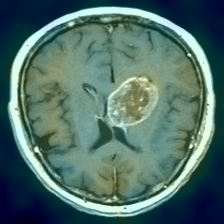

Figure 1: Heatmap Comparison of Unhealthy Images. Different columns show unhealthy MRI images of different positions, sizes, and textures. The first row is the raw image. The second row is the heatmap predicted with PatchCore. The third raw is the heatmap predicted with the proposed method.